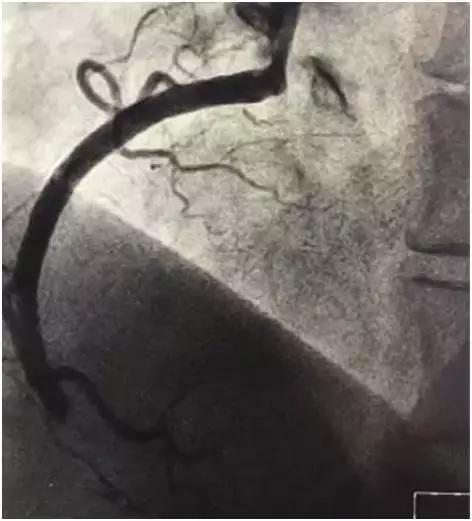

纳闷!5天前冠脉造影无异常,动脉硬化危险因素也少。什么原因导致胸痛?什么原因导致高钾血症?心血管病科立即予积极的降血钾、升心率等对症处理。同时积极术前准备,等待上述李大爷手术完后立即送入导管室,行冠脉造影检查明确右冠脉中段完全闭塞,闭塞处见血栓影。随后进行PCI术,反复血栓抽吸导管于闭塞处抽吸,抽出大量血栓,复查造影示右冠脉完全通畅,无需进行支架植入。术后心律转为窦性,生命体征平稳。

右冠脉造影示:中段完全闭塞

术后右冠脉通畅